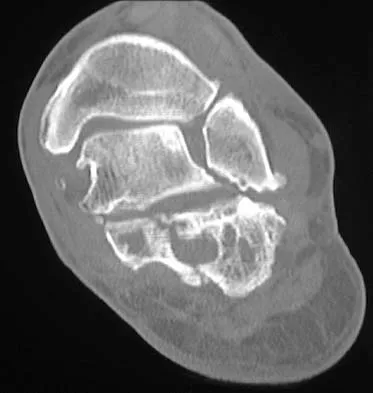

A patient is treated with volar plating for a distal radius fracture. The CT scan shown in Figure 15 is obtained after union of the fracture because the patient reports ongoing symptoms. The prominent hardware is most likely injuring what tendon?

Extensor tendon injuries have been reported after volar plating of distal radius fractures. The CT scan shows prominent dorsal hardware a few millimeters ulnar to Lister's tubercle. The second compartment, the ECRL and ECRB, is radial to Lister's tubercle. The ECU runs along the distal ulna. The contents of the fourth dorsal compartment run just ulnar to Lister's tubercle. The EDC tendon is likely irritated in this patient. The EPB runs along the radial border of the radius and is well away from prominent hardware. Benson EC, Decarvalho A, Mikola EA, et al: Two potential causes of EPL rupture after distal radius volar plate fixation. Clin Orthop Relat Res 2006;451:218-222.